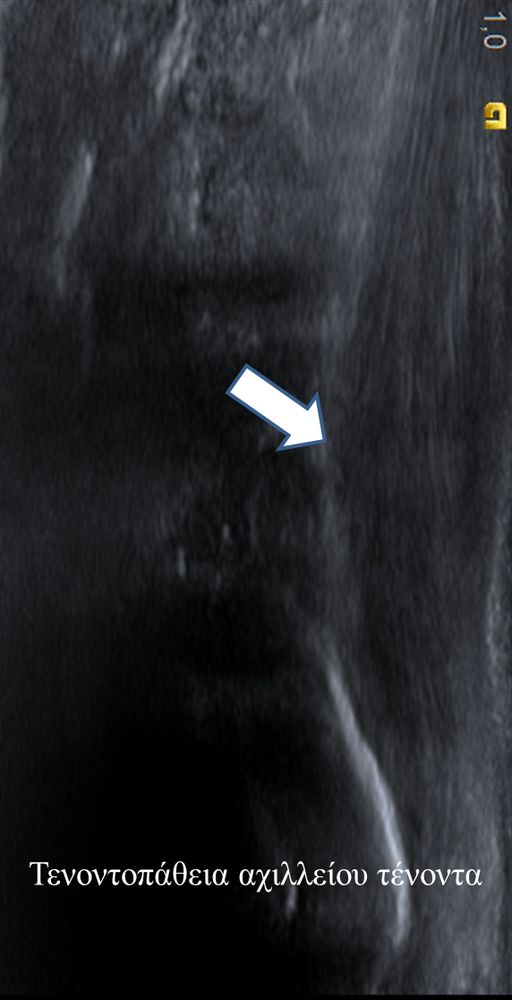

Είναι μια νέα μέθοδος που χρησιμοποιεί υψηλής ευκρίνειας υπερήχους για τη διάγνωση μυοσκελετικών παθήσεων που αφορούν τένοντες, μυς, συνδέσμους, νεύρα και περιφερικές αρθρώσεις. Η μέθοδος αναπτύχθηκε τα τελευταία χρόνια και αποτελεί αναπόσπαστο μέρος στη διαφορική διάγνωση παθήσεων που αφορούν τηνορθοπαιδική, αθλητιατρική, ρευματολογία και παιδιατρική.

Πρόκειται για υπερηχογράφημα υψηλής ευκρίνειας που επιτρέπει την λεπτομερέστατη απεικόνιση (σε επίπεδο χιλιοστού) ακόμη και πολύ μικρών/επιφανειακών ανατομικών δομών και απαιτεί ειδικό υπερηχογραφικό εξοπλισμό καθώς και εξειδίκευση του ακτινολόγου. Η εξέταση γίνεται με δυναμικό τρόπο, δηλ εκτελούνται δοκιμασίες κίνησης του μέλους που πάσχει, ώστε να αποκαλυφθεί η παθολογίαακόμη και όταν δεν είναι εμφανής σε θέση ηρεμίας. Επιπλέον, η εξέταση είναι ανώδυνη και ασφαλής και δεν περιλαμβάνει ακτινοβολία (CT), μαγνητικό πεδίο (MRI) ή παραμονή σε κλειστό χώρο και είναι πολύ ανεκτή τόσο σε ενήλικες όσο και σε παιδιά.